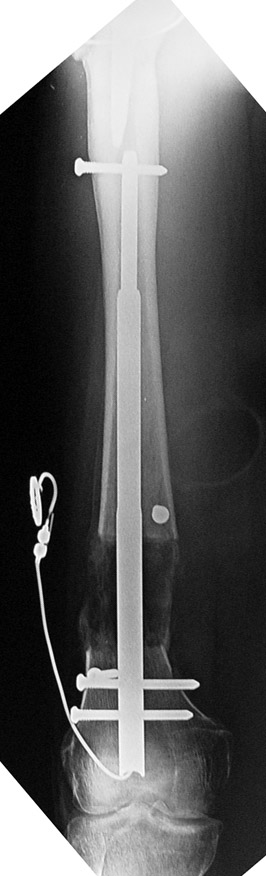

Since 2005 Dr. Mehmet KOCAOGLU is the first most Fitbone operating surgeon in TURKEY. He established the center of excellence for Fitbone surgeries in Istanbul. Fitbone comprises a telescopic nail implant that can extend, powered by an electric motor and controlled by a receiver with an antenna that is buried under the skin; the receiver in turn is controlled by a hand-held radio-frequency transmitter. The procedure for lengthening the lower leg is as follows:

A two-centimetre incision is made at the patient’s knee, and a rimmer is used to create enough space in the bone for a stainless steel nail.

The bone is cut about 14 cm below the knee from the inside with an internal saw. The stainless steel nail is held in place by two screws. The top of the nail is attached to a tiny, plastic-encased receiver that is placed under the skin. The patient controls the lengthening process. By pushing a button on the transmitter when it is placed against the antenna, the built-in motor extends the nail one millimetre per day. When the leg has grown to the desired length, lengthening stops, and the bone is allowed to solidify. The device can be removed about two years after the initial surgery. This procedure, however, comes at a price. While the Ilizarov external fixator costs approximately USD$4,000, and the ISKD implant about USD$8,000, the Fitbone device carries a price tag of roughly USD$15,000 (all prices exclusive of surgery costs).